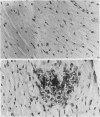

Adult male rabbits were injected i.v. with 100 mg buffered formic acid per kg body weight daily for 5 days with 24 h between the doses. The fifth dose was labelled with 14C-formic acid. Rabbits were killed 1, 2 and 20 h after the last injection. The highest formic acid concentrations were found one hour after the fifth dose. Total formic acid concentrations were always higher than radiometrically measured. The maximum concentrations of formic acid in brain, heart, kidney and liver were roughly similar to the concentration which inhibits half of the cytochrome oxidase activity in vitro. Histological studies clearly demonstrated the histotoxic changes at cellular level. Calcium deposits were detected in all organs of the injected rabbits. They were absent in control animals. It seems that the formic acid metabolism is slow and that it may cause sufficient hypoxic acidosis to allow the calcium influx and cellular damage.